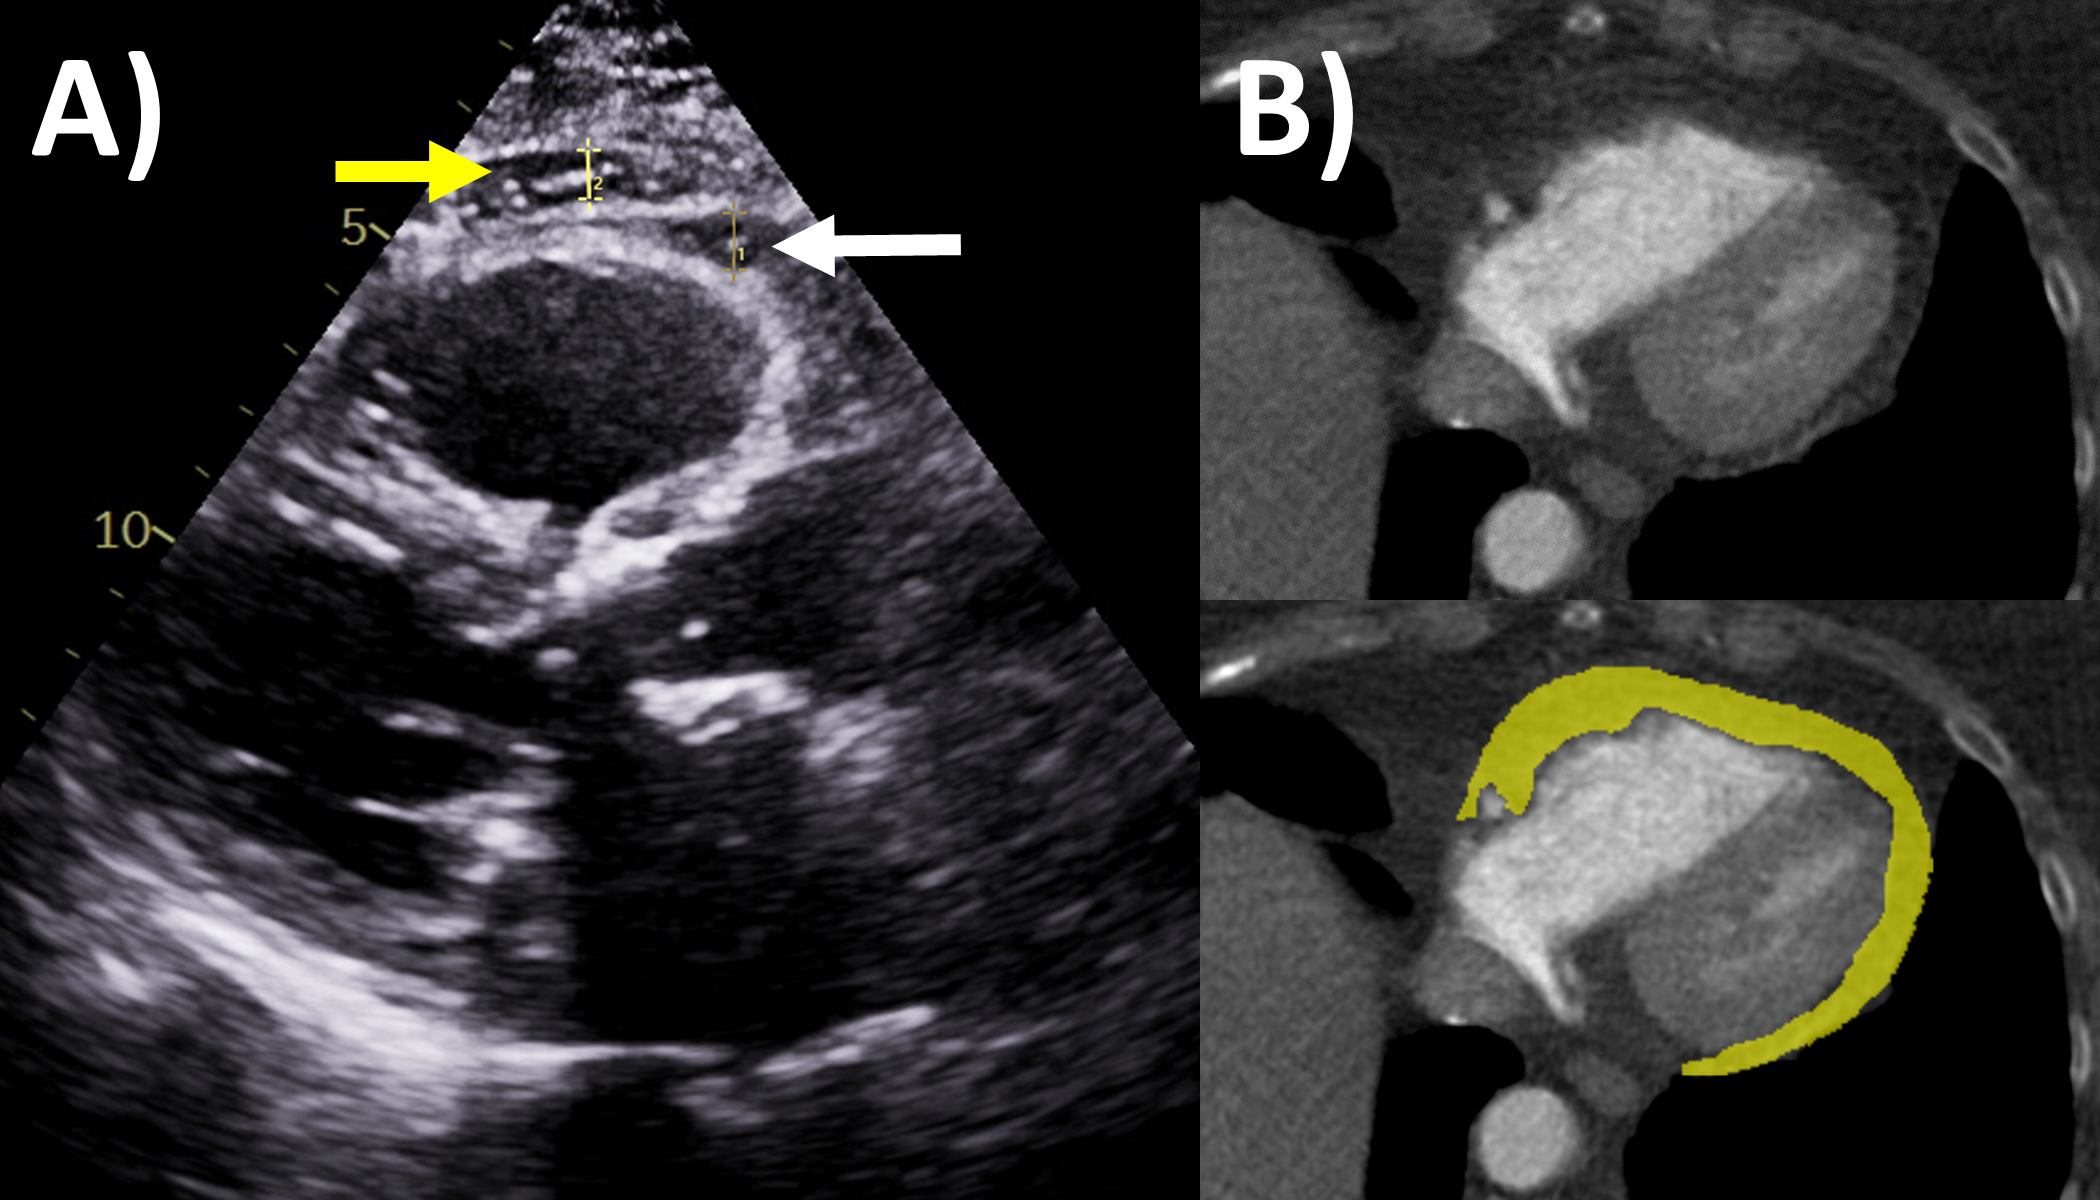

Epicardial adipose tissue accumulation is often associated with increased body mass index and obesity, and has generated significant clinical interest over the last decade because of its relationships and impact on cardiovascular diseases and events [66, 67]. For example, greater epicardial adipose tissue has been implicated in arrhythmias including atrial fibrillation, ectopy and ventricular arrhythmias, heart failure and coronary heart disease in recent studies [68, 69, 70, 71]. Echocardiography can sometimes measure this as the thickness of echo-lucent space between the visceral pericardium and outer myocardium, typically at the right ventricular free wall in end-systole on parasternal long axis view (Fig. 5A), but the method is limited by inability to measure volumes, assess distribution, and operator dependency [72, 73]. Cardiac CT and MRI have improved ability to accurately measure the epicardial fat thickness, volume and distributions that may not be seen by echocardiography [67, 73]. Epicardial fat appears as fat-level hypoattenuation on CT (Fig. 5B), similar to lipomas. CT has additional capabilities to directly assess peri-coronary epicardial fat, along with coronary artery plaque burden and fat attenuation index, which is a marker of perivascular inflammation often observed adjacent to vulnerable high risk coronary plaque. For MRI, epicardial fat is an important mimic of pericarditis and other pericardial masses, and can be distinguished when its signal becomes low when fat saturation pulses are applied such as on delayed enhancement imaging [14]. Nuclear imaging techniques such as fluorodeoxyglucose-positron emission tomography have also shown promise to assess epicardial fat inflammation associated with coronary stenosis [74]. Assessing epicardial fat should be considered when performing the above imaging modalities in the clinical setting, and further research is needed regarding when dedicated imaging to assess epicardial fat should be performed..

Fig. 5.Epicardial fat evaluation by echocardiography and computed tomography. (A) Echocardiography: parasternal long axis view, white arrow is epicardial fat measuring 6 mm, yellow arrow is pericardial fat. (B) Computed tomography: yellow area quantifies the epicardial fat on this axial slice though the ventricles.